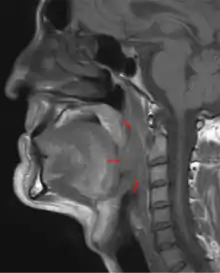

![]() | |

3D medical illustration showing the cancer formation in the tissues of the oropharynx | |